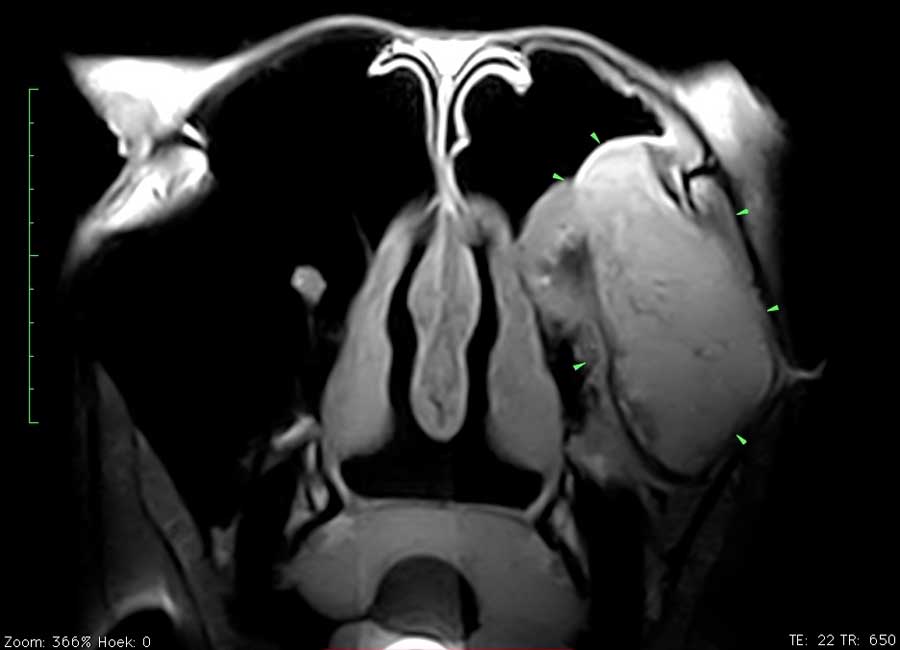

Voorbeeld

Dit paard had sinds enkele weken een unilaterale bloederige neusvloei. Op endoscopisch onderzoek was slechts een minimale afwijking ter hoogte van het linker ethmoid te zien. Bij radiografisch onderzoek was een grote massa in de sinus te zien. Er werd beslist een pre-operatieve MRI uit te voeren om de operatie te plannen en ook prognose beter te kunnen inschatten. Het ethmoid hematoom (PEH) bleek een groot deel van de linker sinus ingenomen te hebben.